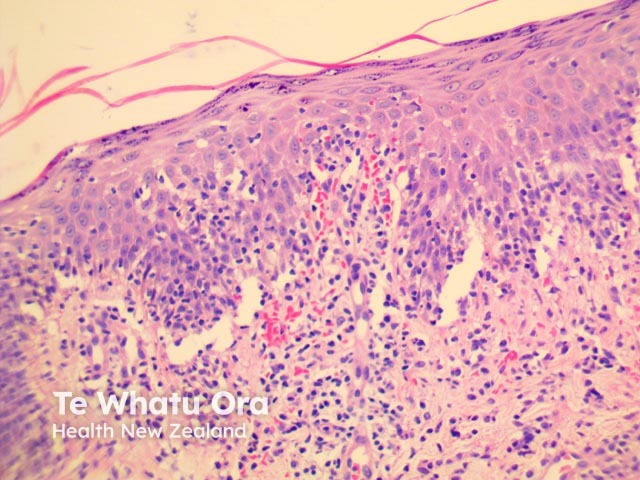

PLEVA has sharply delimited, moderately dense, lymphocytic infiltrate involving the superficial vascular plexus, which extends in a wedge-shaped pattern to involve the lower dermis (figure 1). The superficial dermis shows a dense lichenoid infiltrate and impressive exocytosis of lymphocytes into the epidermis. The overlying stratum corneum shows parakeratosis which may be confluent and contain collections of neutrophils (figure 2). The epidermis shows pronounced hydropic change and foci of keratinocyte necrosis. Scattered extravasated erythrocytes are seen (figure 3).

Figure 1